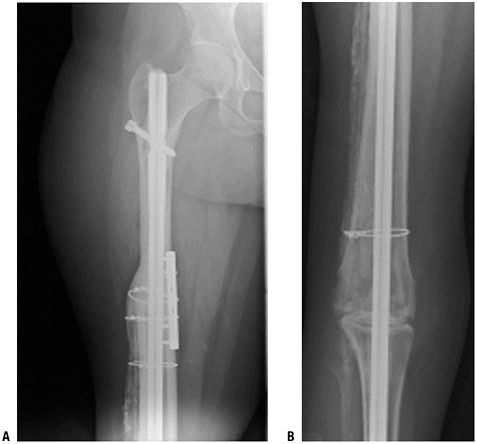

radiographs (A,B) and an axial T1-weighted magnetic resonance image (C). (D,E) Postoperative AP and lateral radiographs.P.70 Figure 4.3-11 (A,B) Figure 4.3-11 (A,B)

In this skeletally immature patient with a proximal tibial Ewing

sarcoma, the tibia was reconstructed using an expandable prosthesis,

maintaining the distal femoral physis. (C)

This specific expandable prosthesis has a deformable resin, which, when

placed in a magnetic coil, allows expansion of the encased preloaded

spring device. The expansion procedure does not require a skin incision.P.71![]() Figure 4.3-12 This patient with Ewing sarcoma of the right scapula shown on plain radiograph (A) and T1-weighted (B) and T2-weighted (C) axial magnetic resonance images underwent scapulectomy and prosthetic scapular reconstruction (D), maintaining the integrity of the proximal humeral metaphysis following neoadjuvant chemotherapy.P.72 Figure 4.3-12 This patient with Ewing sarcoma of the right scapula shown on plain radiograph (A) and T1-weighted (B) and T2-weighted (C) axial magnetic resonance images underwent scapulectomy and prosthetic scapular reconstruction (D), maintaining the integrity of the proximal humeral metaphysis following neoadjuvant chemotherapy.P.72 Figure 4.3-13 A proximal humeral osteosarcoma (A) has been reconstructed using an allograft–prosthetic composite reconstruction (B,C). Figure 4.3-13 A proximal humeral osteosarcoma (A) has been reconstructed using an allograft–prosthetic composite reconstruction (B,C).